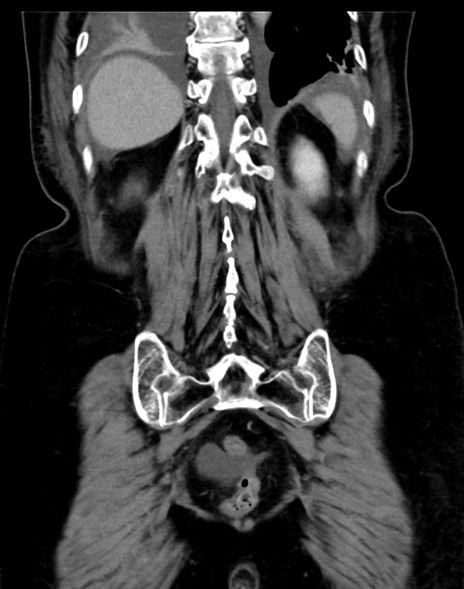

症例13 CT(冠状断像)1日半後